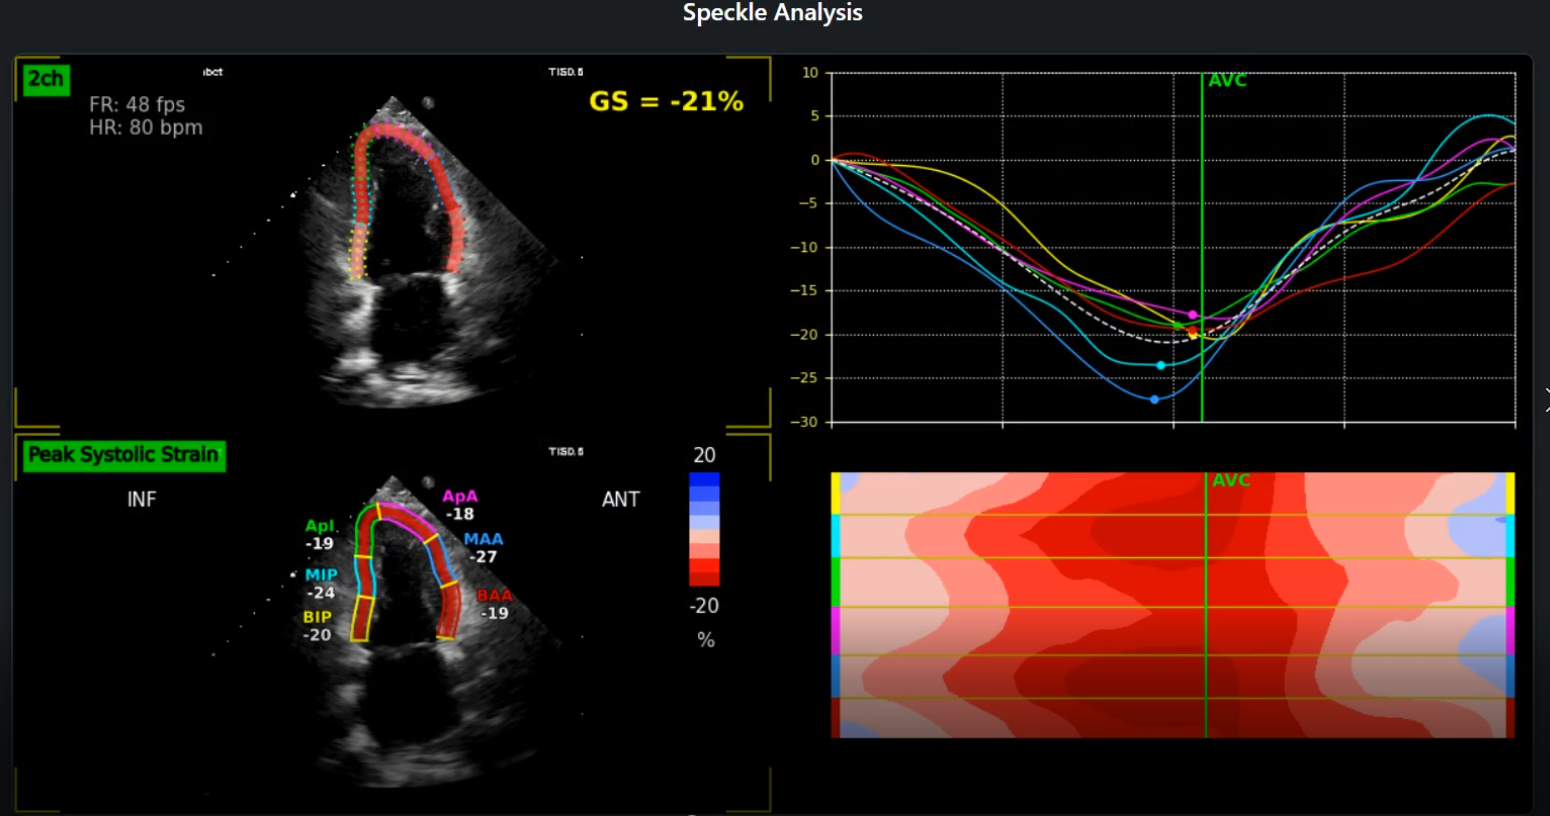

• Global Longitudinal Strain (GLS): Get accurate and reproducible GLS measurements, a key indicator of LV systolic function, aiding in early detection of cardiac dysfunction.